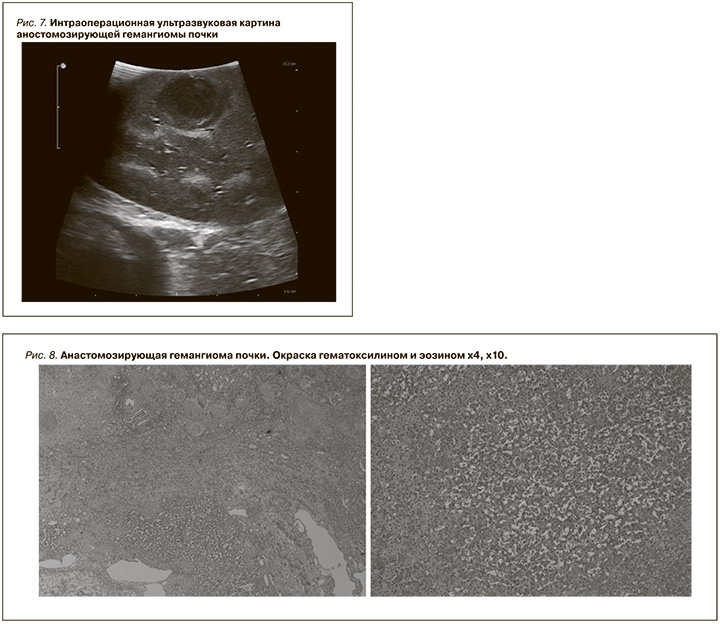

Анастомозирующая гемангиома почки

Сосудистые опухоли относительно часто встречаются в коже и мягких тканях, они крайне редко встречаются в почках, варьируясь от доброкачественных до злокачественных новообразований, которые могут быть диагностически сложными из-за совпадения клинических, морфологических и иммуногистохимических признаков. Эти опухоли включают почечные ангиосаркомы и почечные гемангиомы. В почках описаны различные подтипы гемангиом, включая кавернозные, капиллярные и анастомозирующие гемангиомы [7]. Однако наиболее распространенным подтипом является анастомозирующая гемангиома [7]. Данный подтип опухоли почек представляет собой доброкачественные новообразования, характеризующиеся анастомозирующими сосудистыми каналами капиллярного размера. Эти опухоли встречаются исключительно редко: в литературе сообщается о 75 анастомозирующих гемангиомах [7, 8]. Данные образования встречаются в широком возрастном диапазоне от 10 до 83 лет (в среднем 49 лет) с соотношением мужчин и женщин 2:1 [8]. На КТ гемангиомы часто ограниченны, гиперплотны и неоднородны из-за жировых или неконтрастных гиподенсивных областей и, как правило, демонстрируют накопление контрастного препарата.

Клинический случай 3

Пациент Р. 66 лет госпитализирован в стационар в плановом порядке. Из анамнеза известно, что при обследовании по месту жительства при ультразвуковом исследовании (УЗИ) выявлено образование почки. По данным МСКТ с в/в контрастированием в правой почке в верхнем сегменте определяется образование кистозно-сóлидной структуры с перегородкой в центральной части, активно неоднородно накапливающее контрастный препарат размером до 19 мм (рис. 6).

В плановом порядке пациенту выполнена лапароскопическая резекция верхнего сегмента правой почки с опухолью, продолжительность операции составила 105 минут, время ишемии – 16 минут, стоит отметить, что ввиду внутри-паренхиматозного расположения образования использовалась интраоперационная УЗИ-навигация с разметкой расположения опухоли (рис. 7).

Послеоперационный период протекал без осложнений, на 3-е сутки пациент выписан из стационара. По данным гистологического исследования: фрагменты ткани почки с ростом опухоли сóлидного строения и мономорфных клеток со слабополиморфными ядрами, в опухоли многочисленные анастомозирующие кровеносные сосуды, разделенные соединительно-тканными прослойками. Морфологическая картина анастомозирующей гемангиомы почки (рис. 8).